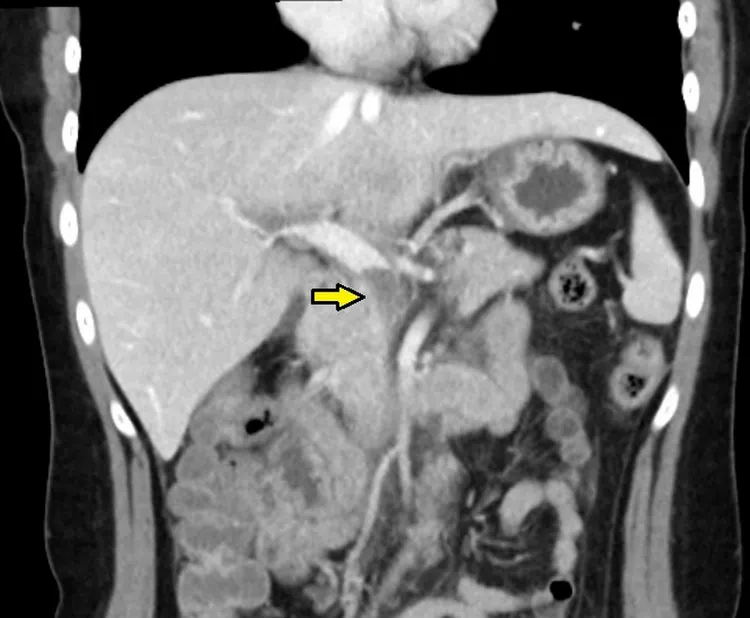

電腦斷層顯示,病人三條靜脈交會處有嚴重血栓。台北慈濟醫院提供